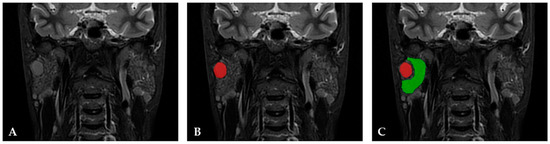

2.3. Texture Analysis Protocol and Statistical Analysis

2.3.1. Image Preprocessing and Segmentation